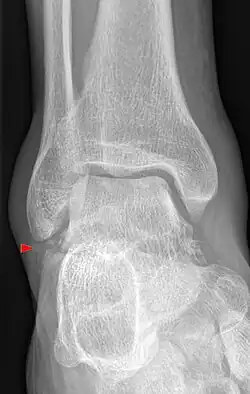

Die Verletzung stellt sich mit Schmerzen und Schwellung in der Fußwurzel und außen am Fuß dar. Diese Befunde können leicht mit einer Verstauchung, Zerrung oder einem Bänderriss am Außenknöchel verwechselt werden. Dieses insbesondere, wenn nicht bekannt ist, dass es sich um einen Snowboarder handelt. Auch ist der Knochenbruch auf Übersichtsröntgenbildern manchmal schwer zu erkennen. Eine Computertomographie kann die Bruchlinien überlagerungsfrei darstellen und ist für die Planung der richtigen Therapie hilfreich.[6][14][7][12]